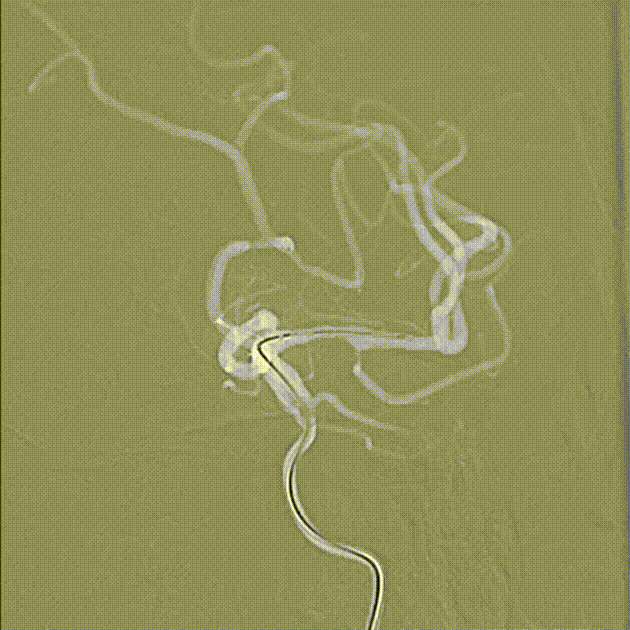

经6F中间导管,微导丝到位后引导Fastunnel®输送型球囊扩张导管到位至左侧大脑中动脉狭窄部位。

Fastunnel®输送型球囊扩张导管打压成形扩张狭窄病变部位,压力8atm,随后造影可见成形满意。

撤出微导丝后,经Fastunnel®输送型球囊扩张导管送入3.0mm*16mm NeuroStellar®颅内支架,支架到位后调整释放张力后定位支架。

术中缓慢释放NeuroStellar®颅内支架头端后系统稳定,随后释放至支架尾端,造影提示支架打开满意,贴壁满意。